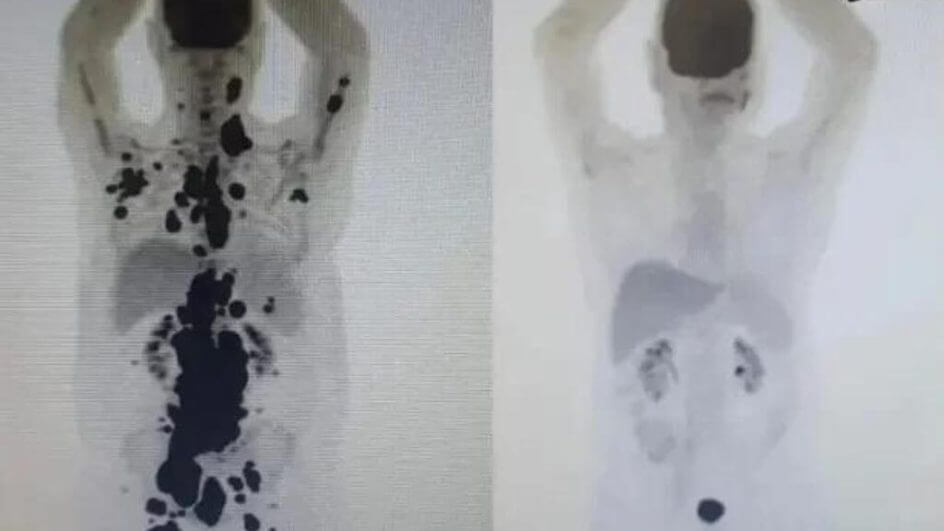

Em entrevista ao Metrópoles, Peregrino disse que a felicidade após a alta médica contrasta com todo o medo que rondou o tratamento. A imagem de seus exames tomográficos, por exemplo, que mostrou a evolução rápida do tratamento, ainda não tinha sido vista por ele.

— Eu nem tinha visto aquelas imagens do exame de março. Se alguém tivesse mostrado para mim aquela imagem talvez tivesse perdido 50% da minha fé e da minha esperança, da minha crença que a ciência iria me ajudar naquele momento — diz Peregrino.